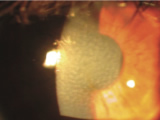

角膜変性症はレーシックを受けると、角膜が白く濁るなど、視力が低下する病気です。眼科専門医の診断でも、角膜変性症未発症の遺伝子保持者の診断は不可能です。アベリーノユニバーサルテストでは、角膜変性症を100%見つけることができます。最近”角膜変性症の診断をしている”と他のクリニックで宣伝をしているようです。角膜変性症は遺伝子疾患ですので、DNA検査を行わない角膜変性症の診察は確実に診断することができません。当院ではこの認定証をアベリーノ社より頂いておりますので、安心してレーシックを受けて頂けることができます。

眼科専門医の診察でも角膜変性症未発症の遺伝子保持者の診断は不可能なため、当院は「臨床試験結果、特異度・敏感度共に100%」、唯一無二のアベリーノユニバーサルテストを導入しています。角膜変性症は、症状が進行した場合視力の大幅な低下に繋がります。

また角膜移植後も再発する疾患です。当院では患者様に安心・安全にレーシックを受けて頂く必須の

検査をしています。